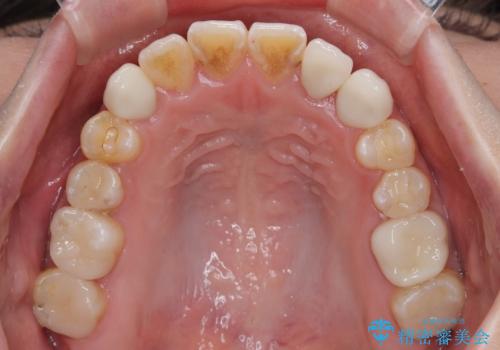

急速拡大が奏効し、非抜歯矯正にて八重歯を解決することができました。

矯正治療後半で結婚式を挙げられたそうですが、参列された方々からは綺麗に整った前歯に大変驚かれたそうで、非常に満足されていらっしゃいました。

矯正治療後は全顎的にむし歯が多いため、セラミッククラウンやインレーにより補綴治療を行うこととしました。